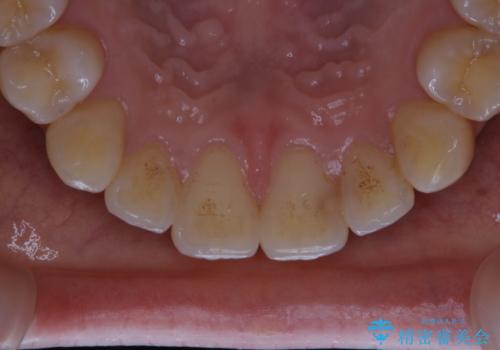

- インビザラインでのマウスピース矯正が終了したため、きれいにクリーニングして口元を明るい印象にしたいとのことでした。PMTC60分コースを行いました。

矯正治療が終わり、せっかくきれいになった歯並びも、虫歯・歯周病などになってしまっては元も子もありません。

矯正治療やセラミックなどによる被せ物の治療終了のタイミングではクリーニングを行い、汚れや着色の除去、歯と歯の間・歯と歯肉との境目などのケアをしっかりすることをおすすめしています。